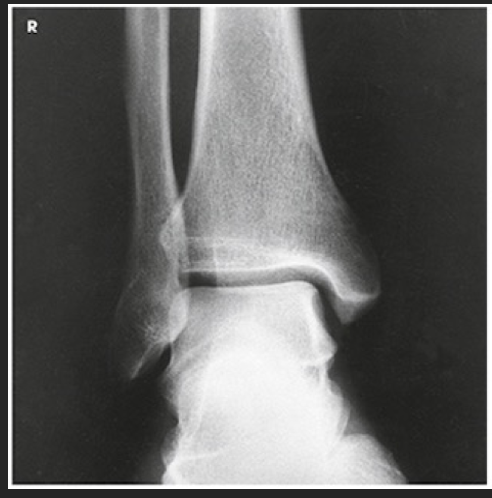

Name this projection.

AP oblique ankle

State the degree and type of rotation used.

45 degrees medially

Where does the CR enter?

Perpendicular to the ankle; midway between the malleoli

Which aspect of the ankle is best visualized?

Lateral

Which joint space must be open?

Distal tibiofibular joint

AP oblique mortise joint

15-20 medially